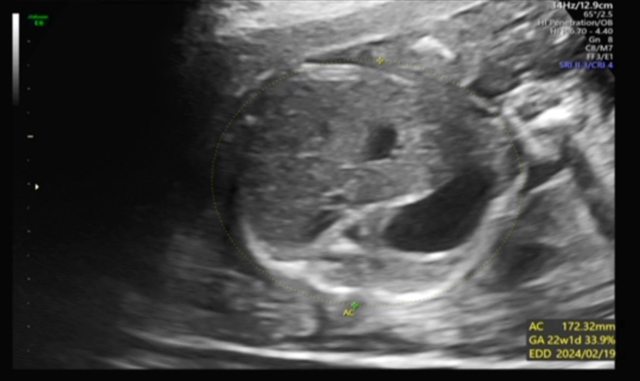

昨天去產檢,醫生覺得寶寶的胃偏大之後要注意觀察 我搜尋了一下好像只有看到胃太小的文,請問大家有沒有遇過類似情況? 我後來看了一下22週的高層次照片,那時候寶寶也是胃大大的,但那時只說是寶寶可能剛 吃飽 https://i.imgur.com/amlKp09.jpg